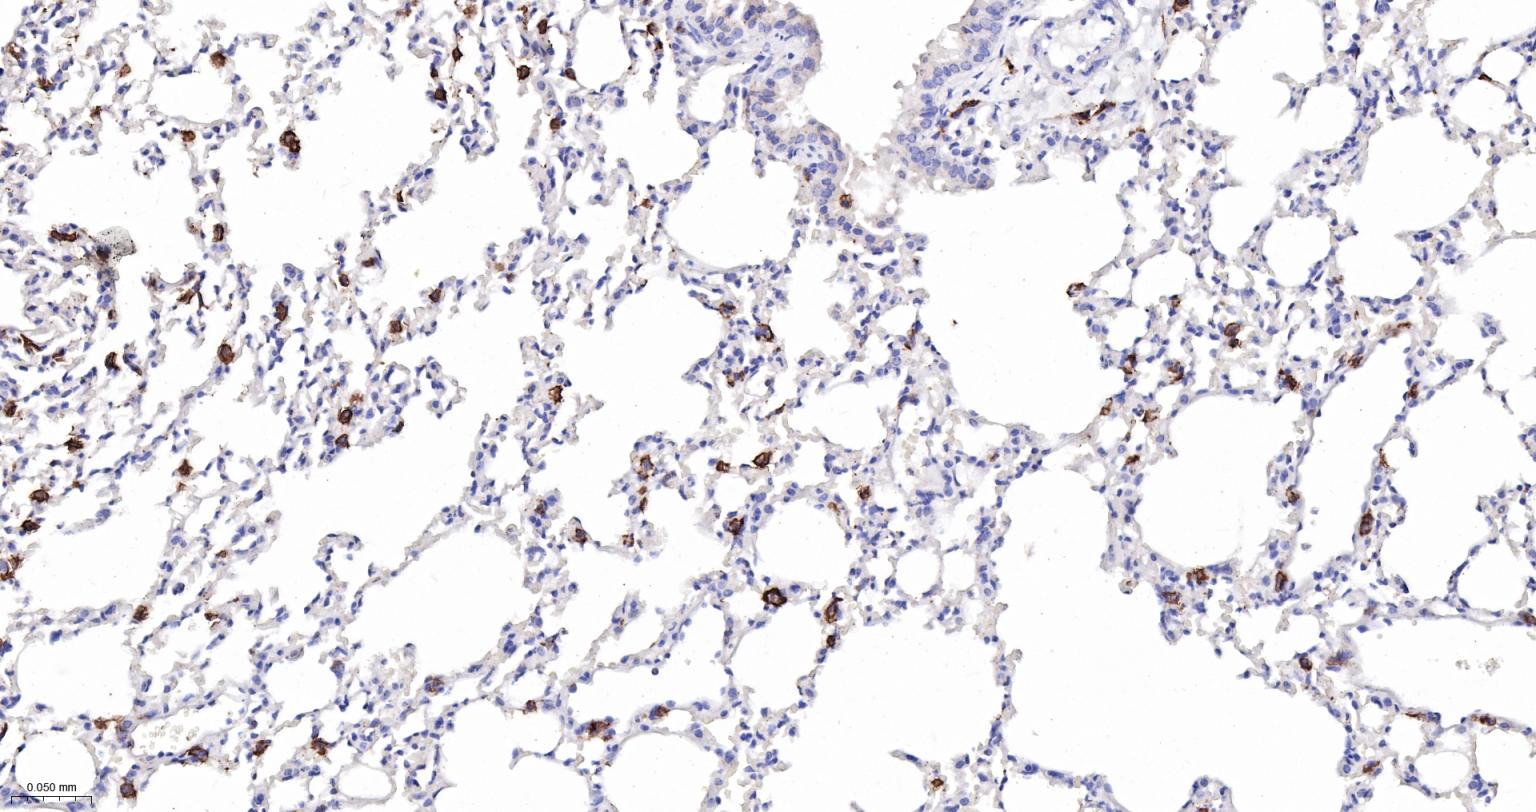

| IHC-P | Mouse | 1:200-1000 | |

交叉反应: Mouse